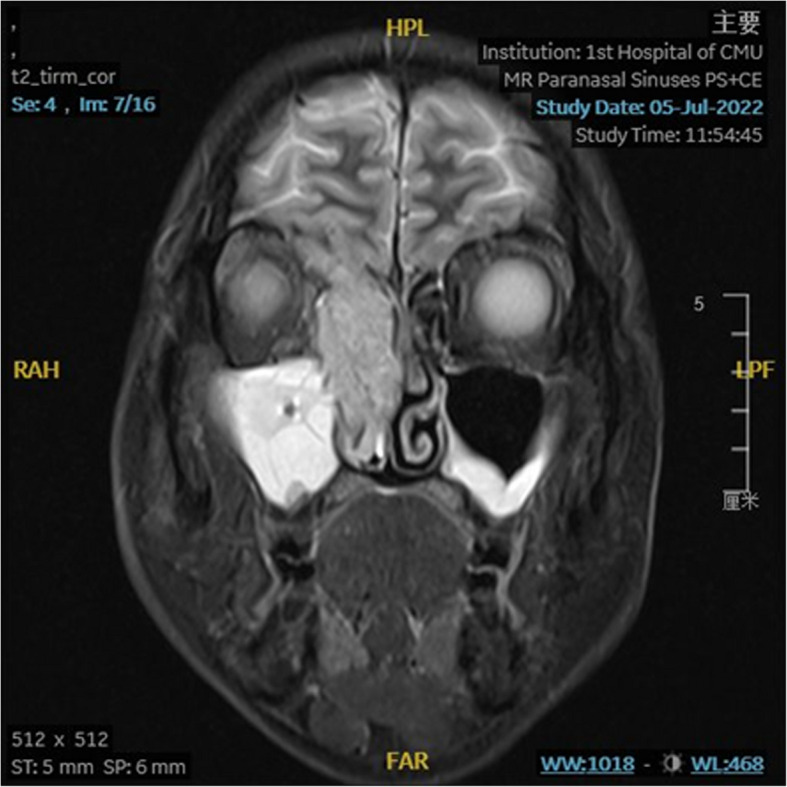

Patient concerns: A 58-year-old male patient with right nasal cavity mass, he complained for persistent right-sided nasal congestion for 3 months, accompanied by decreased sense of smell and protrusion of the right eyeball.

Outcomes: The patient was followed up for 22 months with interval nasopharyngeal MRI and lung CT scan, with no sign of tumor recurrence or metastasis.